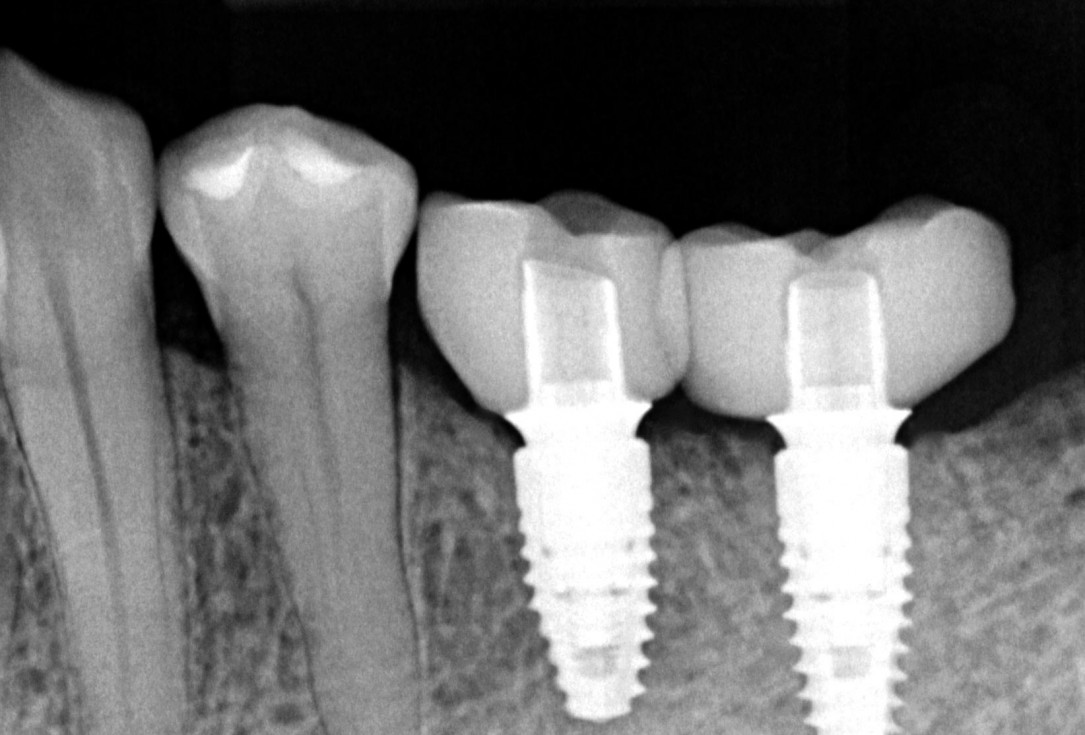

Three implants placed in a narrow posterior mandible